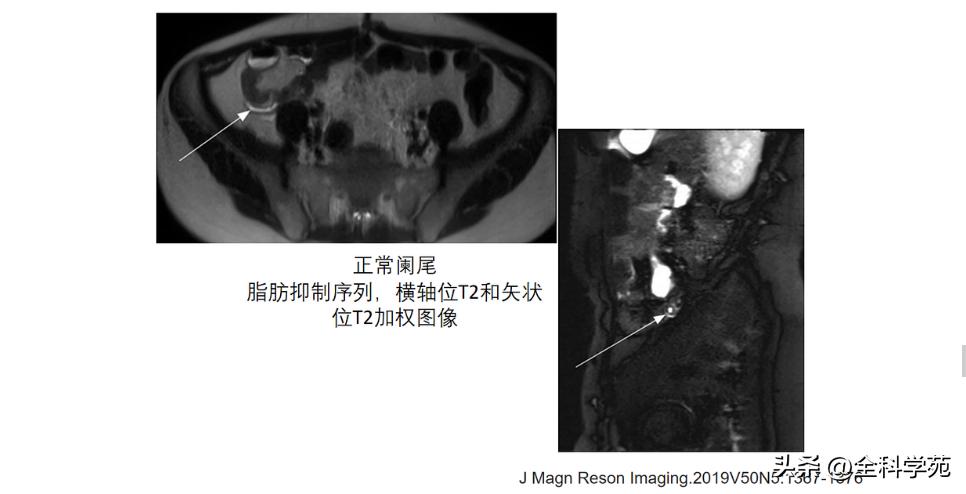

MRI: T1低信号,T2高信号,DWI: 扩散受限

◆ 阑尾周围脂肪密度增高/模糊与腹腔其他部位的脂肪比较,CT表现为脂肪密度增高,T2压脂为高信号